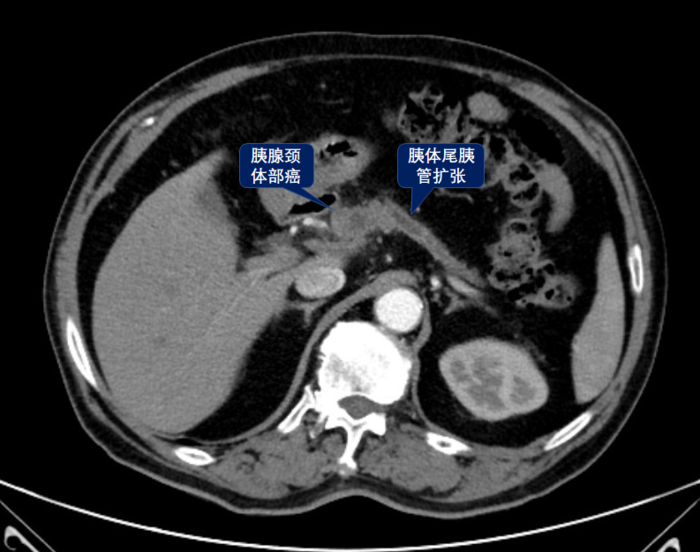

胰腺癌,一般指胰腺导管上皮腺癌(PDAC),好发于中老年人,临床上可以有新发糖尿病、背痛、黄疸等表现,影像学特点是乏血供肿块伴有胰管扩张、胰腺实质萎缩,容易侵犯胰腺周围血管,恶性程度高、预后差,有特异性肿瘤标记物Ca199。病理特点可以胰腺组织内基本结构被破坏,异型腺体浸润性生长,侵犯神经,间质纤维组织增生。尽可能早发现早手术(但是太难了),如不能手术,则应通过辅助化疗或放化疗结合降期,以达到手术时机。?